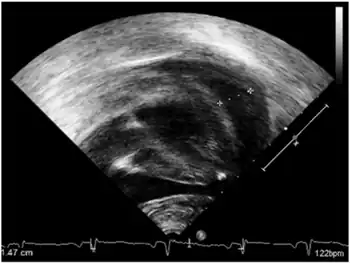

- Early onset-pericardial effusion